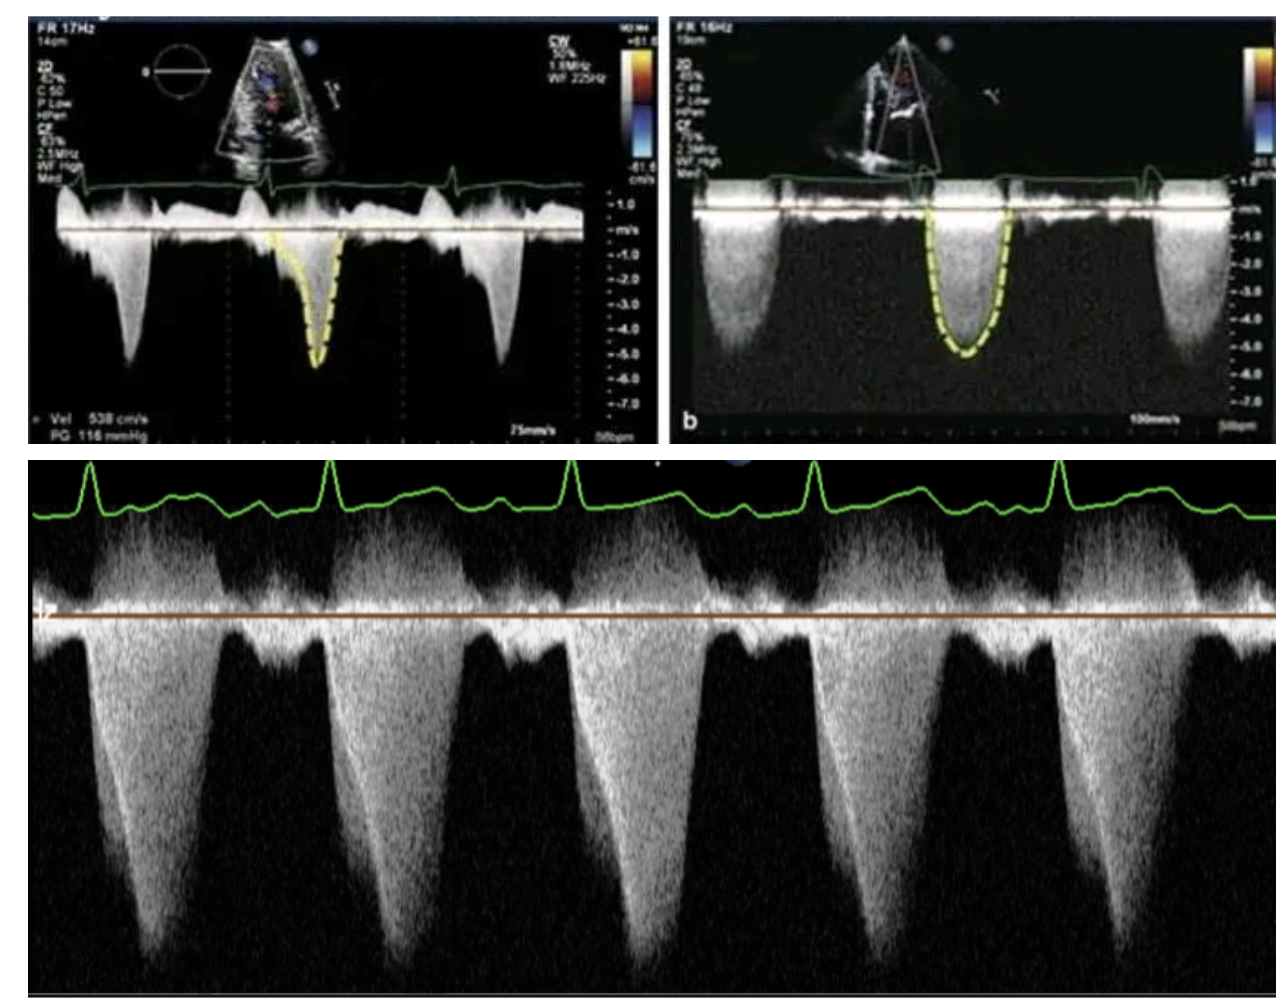

Pulse Wave Doppler can help measure the RVOT velocity and VTI (Velocity Time Integral)

Continuous Wave Doppler can help determine type of RVOT obstruction:

• Dynamic (A): late-peaking “lobster claw” or dagger-shaped Doppler signal

• Fixed/Supravalvar (B): mid-systolic peak, more symmetric Doppler signal

• Obstruction in series (C): overlapping Doppler patterns

Obstruction in Series is most common in TOF as there is dynamic narrowing below the pulmonary valve with fixed stenosis along the pulmonary valve or main pulmonary artery.

A (Top Left): Dynamic Obstruction

B (Top Right): Fixed Obstruction

C (Bottom): Obstruction in Series